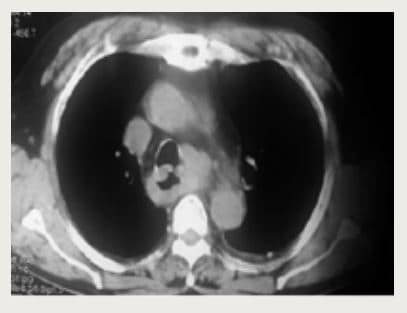

Paciente varón de 75 años de edad, natural y procedente de Lima, con antecedentes de osteoporosis y osteoartritis. Inicia los síntomas 18 meses antes del ingreso, de manera insidiosa y progresiva con disfagia a sólidos, odinofagia y náuseas intermitentes. Cinco meses antes del ingreso, el paciente manifestó que los síntomas disminuyeron; sin embargo, tres meses antes presenta repetidos episodios de melena. Además, dos meses antes presentó una pérdida de peso progresiva de aproximadamente 13 kg. Un mes antes del ingreso se agrega tos con expectoración sanguinolenta y epigastralgia, motivo por el cual decide acudir a consulta externa del hospital EsSalud Angamos, donde se le solicita una tomografía de tórax con contraste (Figura 1). Asimismo, se le realizó una endoscopía que informa mucosa del tercio proximal con lesión irregular, proliferativa, que obstruye la luz, erosionada y friable. No se pudo tomar biopsia, pero se piensa en un posible diagnóstico de neoplasia maligna de esófago.

Figura 1. En los dos tercios inferiores del esófago y en la región pericardial se evidencia engrosamiento neoformativo que se asocia a múltiples adenopatías peritumorales, derrame pleural laminar bilateral y no se evidencian nódulos pulmonares. No lesiones significativas en el tórax.